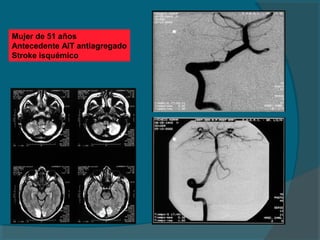

Mujer de 51 años

Antecedente AIT antiagregado

Stroke isquémico